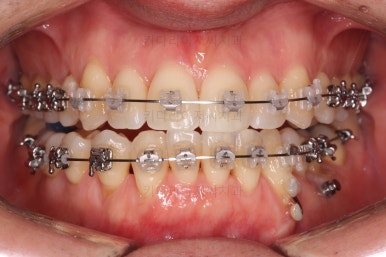

윗니도 장치를 부착했어요.

아랫니보다 해야 할 작업이 많지 않기 때문에 이렇게 시간차를 두어 진행을 했고, 이렇게 하면 교정장치가 눈에 띄는 기간이 줄어들어 환자분의 만족도는 더 올라가게 되죠.

아랫니 이 뽑은 자리는 거의 다 다물렸어요.

거꾸로 물리는 앞니도 어느 정도 많이 개선이 되었고요.

이 정도 진행되면 입매에 대해서 평가를 합니다.

외모도 좋아졌고 교합도 개선되어 가고 있기 때문에 좀 더 정교한 마무리를 하고 치료 종료하기로 했어요. 모자렀던 부분도 더 가지런하게 하고 있어요.

점점 마무리에 가까워지고 있습니다.